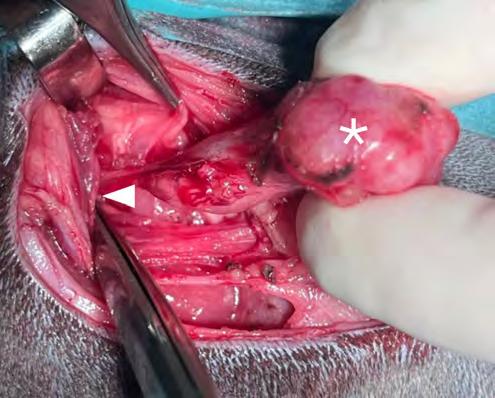

preanestésica con butorfanol y la inducción anestésica con alfaxolona a las mismas dosis anteriormente indicadas, el paciente se intubó con un tubo de 2,5 de diámetro con manguito y se mantuvo con sevofluorano al 2-3 % (SevoFlo 100 %, Zoetis Louvain-La-Neuve, Bélgica) con oxígeno al 100 % en un circuito abierto (T de Ayre) y respiración espontánea. En la exploración abdominal mediante laparotomía media, se observaron

los linfonodos mesentérico caudal, sublumbar e ilíacos pálidos y de aspecto granuloso. Se tomaron muestras de estos linfonodos para histopatología y cultivo. Se realizaron lavados y aspiración de la cavidad abdominal con solución salina y se cerró por planos de forma rutinaria. El paciente se recuperó de manera satisfactoria.

El estudio histopatológico mostró una linfadenitis piogranulomatosa grave y generalizada; la totalidad de los fragmentos evaluados estaban ocupados por múltiples piogranulomas compuestos por centros de tejido necrótico y neutrófilos degenerados rodeados por abundantes macrófagos, células linfoplasmocitarias y fibroblastos reactivos. No se visualizaron microorganismos. La muestra fue positiva al RT-PCR (Real Time Polymerase Chain Reaction) del coronavirus entérico del hurón (FECV). El cultivo microbiológico resultó negativo. El diagnóstico de enfermedad por coronavirus sistémico del hurón (FSCVD) se confirmó mediante el análisis inmunohistoquímico frente al coronavirus felino del linfonodo mesentérico remitido. El anticuerpo utilizado presentaba positividad cruzada con el FSCV (Idexx laboratorios, Barcelona, España) (Fig. 2).